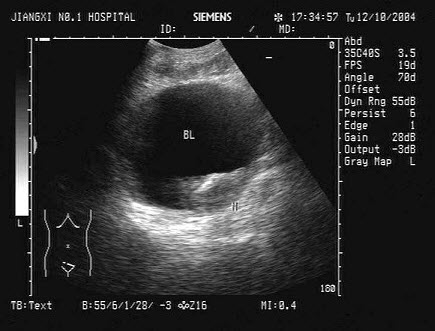

44、单项选择题

男性,45岁,因出现无痛性血尿半月余就诊,根据超声声像图提示,最可能的诊断是()

A.肾细胞癌

B.肾结核

C.肾囊肿

D.肾脓肿

E.肾结石